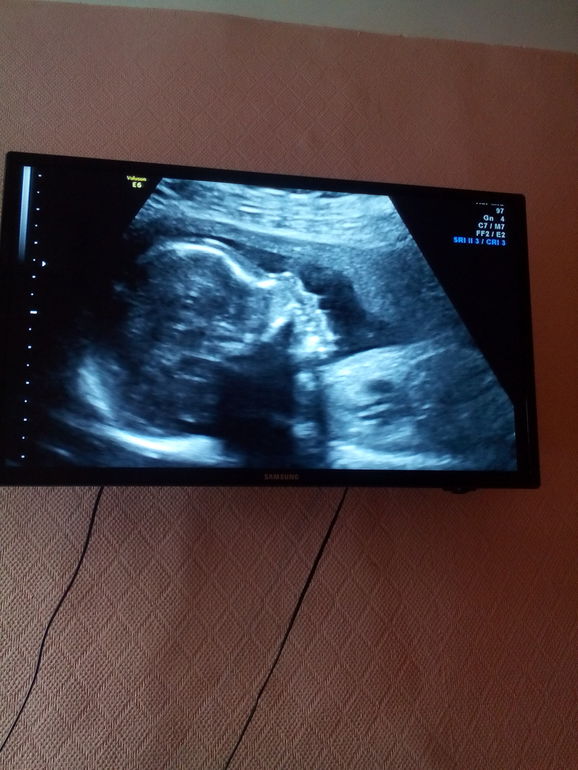

второй скрининг!!!!!!!!20 недель!

дождалась я скрининга!!!! второго сыночка нам подтвердили)))на фото такой же курносый как и Егорка)))) весим 380 грамм. все параметры в норме!!! Растем дальше! прибавка в весе 6 кг.